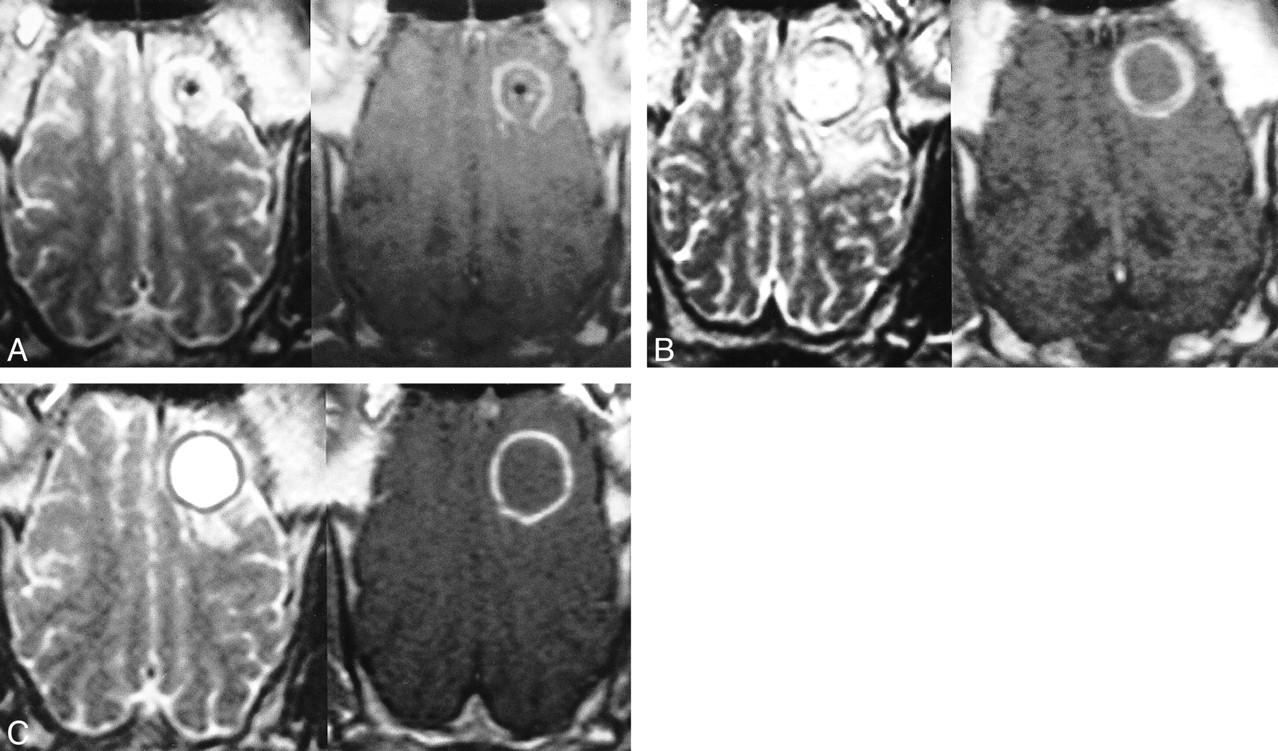

MR images of the brain obtained immediately and at 3, 7, and 14 days after cryotherapy showed spherically shaped lesions of different sizes and appearances. Immediately after the freezing, the cryolesions were isointense to the adjacent brain tissue but were surrounded by a hyperintense edematous ring on T2-weighted sequences (Fig 6A). On fluid-attenuated inversion recovery images, a beginning edema surrounding the cryolesion was observed. On contrast-enhanced T1-weighted images, the lesions were isointense to the adjacent brain but surrounded by a thin, contrast-enhanced rim, representing a disruption of the blood-brain barrier. The size of the ice ball and the lesion extensions were in good accordance. No statistically significant difference was observed. Three days after the intervention, the center of the lesions turned into an inhomogeneous hyperintense signal, and the diameter of the lesions increased to nearly 135% on T2-weighted images as compared with the initial size of the ice ball. On fluid-attenuated inversion recovery images, the lesions were embedded in an inhomogeneous and irregularly shaped zone of edema. The diameters of the cryolesions, including the total extension of the edema, increased to nearly 150% of their original size. On contrast-enhanced T1-weighted images, the diameters of the cryolesions, including the contrast-enhancing rim, increased slightly but not more than 15%. The increase of lesion size 3 days after cryotherapy was statistically significant for all sequences (P < .04). Seven days after cryotherapy, the size of the lesions decreased on T2-weighted images to 120%, as compared with the initial ice ball size (Fig 6B). A thin signal-free rim surrounding the hyperintense lesion was observed, representing a thin layer of hemosiderin. On fluid-attenuated inversion recovery images, the edema decreased slightly to 125%, as compared with the ice. On contrast-enhanced T1-weighted images, the diameter of the lesions, including the contrast-enhancing rim, decreased to 108%. The differences in size compared with the initial diameter of the ice ball were significant only for T2-weighted and fluid-attenuated inversion recovery sequences. Fourteen days after freezing, the lesions appeared homogeneously hyperintense on T2-weighted images and the ring of hemosiderin was seen more clearly (Fig 6C). On the fluid-attenuated inversion recovery images of most of the animals, the surrounding edema disappeared. On contrast-enhanced T1-weighted images, the lesions were sharply delineated by a thin rim of disrupted blood-brain barrier. Fourteen days after cryotherapy, no statistically significant difference in lesion size compared with the size of the initial ice ball was observed on fluid-attenuated inversion recovery, T2-weighted, or contrast-enhanced T1-weighted images.

A, Axial plane T2-weighted turbo spin-echo (left) and contrast-enhanced T1-weighted spin-echo (right) images obtained immediately after the freezing. A spherically shaped ring of edema around an isointense cryolesion is visible (left). On the contrast-enhanced image (right), the disrupted blood-brain barrier in the location of the previous interface of frozen and unfrozen brain tissue is visible. Hemorrhage within the lesion can be seen. An inactive cryoprobe is still left in situ.

B, Seven days after therapy, the cryolesion appears inhomogeneously hyperintense, surrounded by an inconstant thin rim of hemosiderin (left). Edema in the adjacent white matter can be seen. Thickening of the zone of the disrupted blood-brain barrier is visible on the contrast-enhanced image (right).

C, Fourteen days after cryotherapy, the cryolesion appears homogeneously hyperintense on the T2-weighted image (left). The rim of hemosiderin decreased further in signal intensity and surrounds the lesion entirely. The edema outside the cryolesion disappeared incompletely. After the administration contrast medium (right), the zone of disrupted blood-brain barrier decreased in thickness, enabling a sharp delineation of necrosis and viable brain tissue.